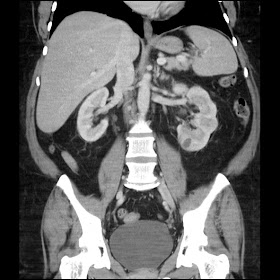

Acetabular Retroversion

Acetabular retroversion is associated with "pincer" type FAI. See excellent explantion here (link and images with permission from the author):